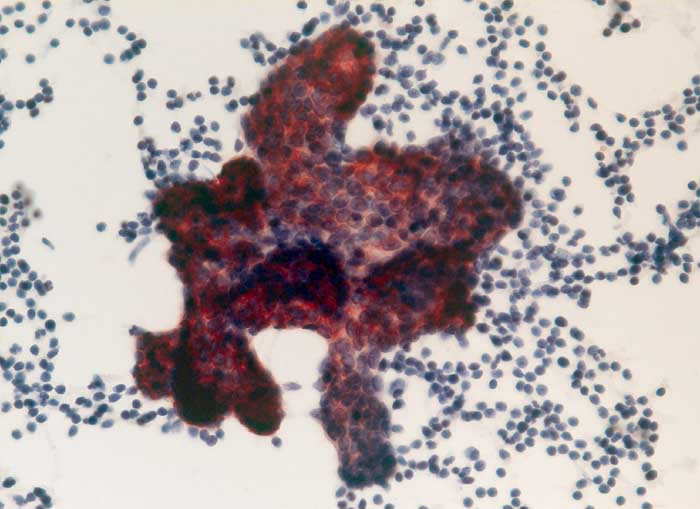

Pleurametastasen eines papillären Nierenzellkarzinoms

Pleuraerguss Zytologie

Pleuraerguss: der papilliforme Tumorzellverband ist positiv für den epithelialen Marker BerEP-4.

Immunzytochemisch sind die papilliformen Zellverbände deutlich positiv für den Epithelmarker Ber-EP4, dagegen negativ für den Mesothelmarker Calretinin. Demnach handelt es sich nicht um reaktive Mesothelproliferate, sondern um Karzinomzellen, vereinbar mit Metastasen des bekannten papillären Nierenzellkarzinoms.

Metastasierendes papilläres Nierenzellkarzinom. Lungenmetastasen seit 2 Jahren bekannt.